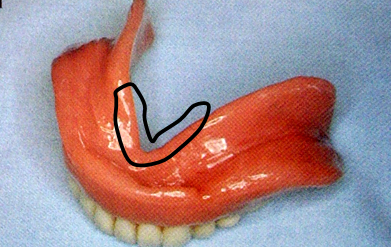

6.磨牙后垫(retromolar pad)

位于下颌最后磨牙牙槽嵴远端的粘膜软垫,覆盖在磨牙后三角上,由疏松的结缔组织构成,含黏液腺。

磨牙后垫的形态和位置比较稳定,作为排人工牙时的解剖标志;垂直向:下颌第一磨牙的颌平面与磨牙后垫的1/2处等高;

前后向:下颌第二磨牙应位于磨牙后垫前缘;

颊舌向:磨牙后垫颊面、舌面向前与下颌尖牙的近中面形成一个三角形。